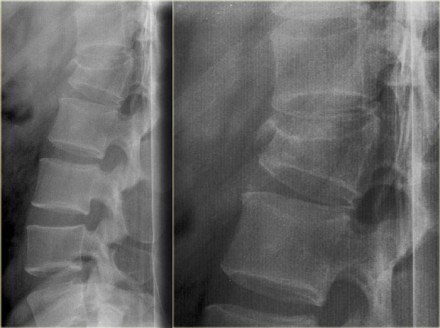

Jumper's fracture

On the left a fracture of the calcaneus and a lumbar spine fracture.

This is called a 'jumpers fracture' or a 'lover's fracture', because it

is usely seen in people jumping out of a window to escape from the

police or a jealous husband.

In this case it is clear that we are looking at an unstable fracture, because this is a burst fracture.

Both the anterior and the middle column are disrupted.

In addition there is edema in the posterior soft tissues indicating that there is also involvement of the posterior column.

Notice also the marrow edema in the adjacent bodies due to the severe axial loading.